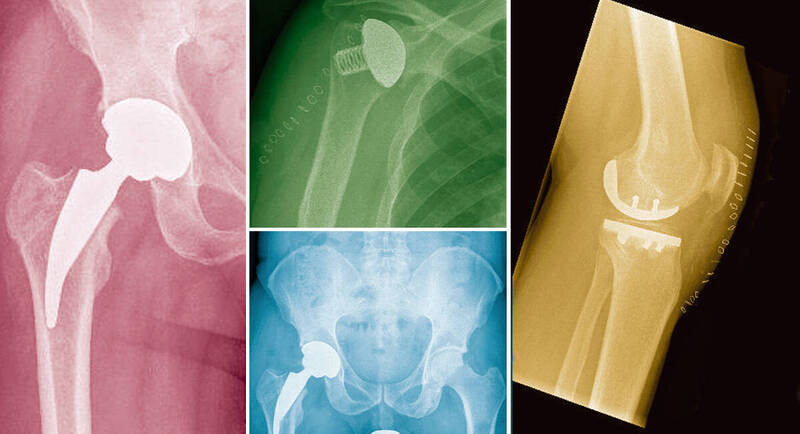

Sowohl der Trend zur Spezialisierung als auch das hohe Anspruchsdenken der Patienten bedingen die Bildung von Zentren, in welchen Spezialisten verschiedener Gebiete miteinander kooperieren, um diagnostische Möglichkeiten mit modernen therapeutischen Verfahren zum Wohle des Patienten zweckmäßig zu verbinden und die Behandlungsstrategie zu optimieren. Dies war für uns Anlass Partner zu suchen, mit denen wir über die Möglichkeiten des Krankenhauses Bischofswerda hinaus, die Behandlung von Gelenkerkrankungen, speziell des Schulter-, Hand-, Hüft- und Kniegelenkes, verbessern können.

Im Zertifizierten EndoProthetikZentrum arbeiten Fachärzte für Orthopädie und Unfallchirurgie mit ambulant tätigen Fachärzten für Radiologie, Orthopädie und Handchirurgie eng zusammen. Somit gibt es eine Vernetzung von ambulanten und stationären Leistungen. Problemfälle werden in einer Expertenrunde vorgestellt und diskutiert, um für die jeweiligen Patienten die bestmögliche Lösung zu finden.

Behandlung des femoroacetabulären Impingements. Endoprothetische Versorgung bei Coxarthrose oder Femurkopfnekrose mit auf das Patientenalter abgestimmten endoprothetischen Verfahren und entsprechenden Gleitpaarung

Navigationsgestützte Endoprothetik des Kniegelenks. Spezialisiert auf die Implantation individuell gefertigter Knieendoprothesen, von der Schlittenprothese bis zum totalen Obeflächenersatz - seit 2008.